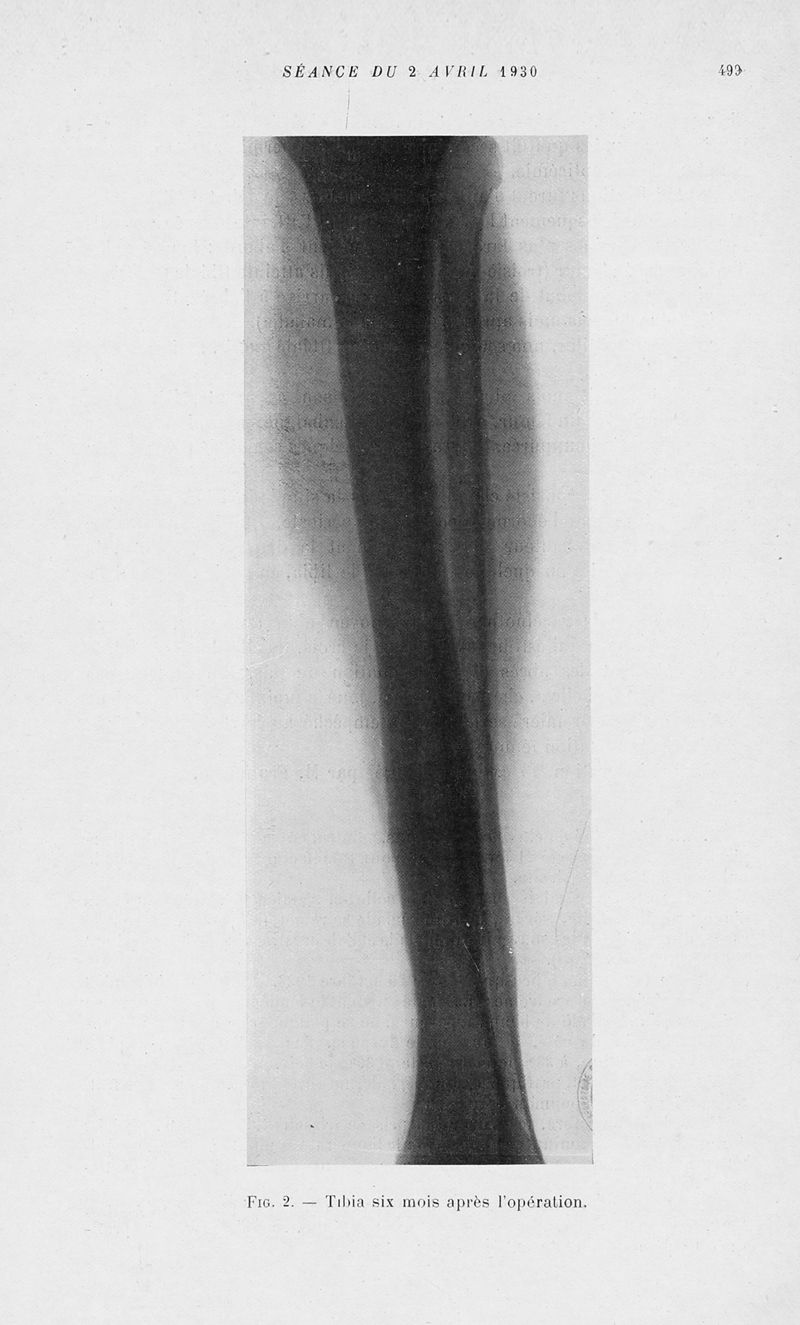

Bulletins et mémoires de la société nationale de chirurgie

Tome LVI, 1930. - Paris : Masson, 1930.